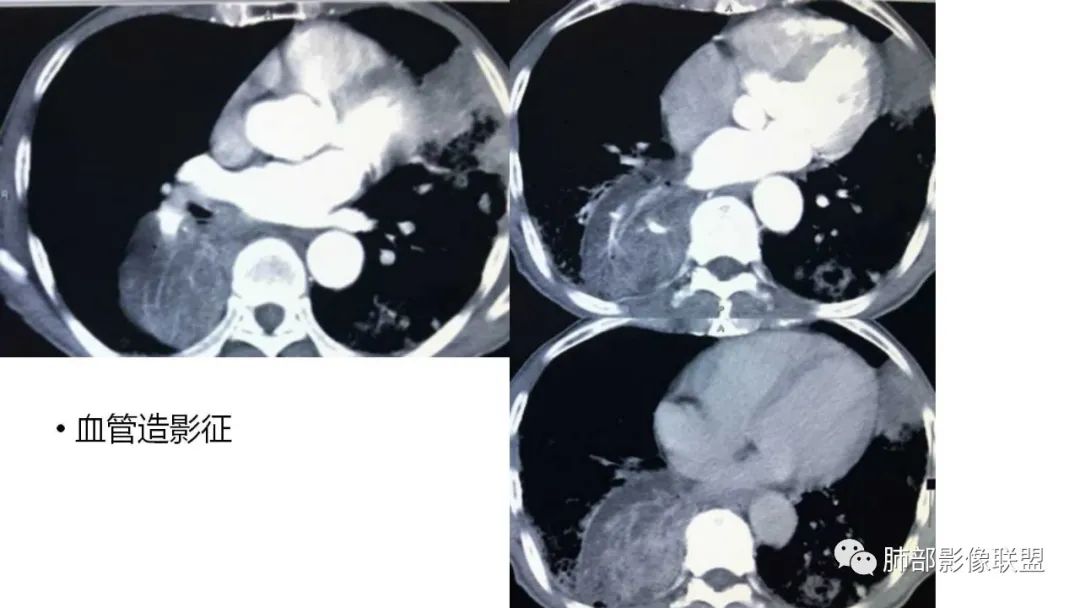

4、增强后不均匀强化,存在低强化区呈弱强化或无强化,因此可见“血管造影征。”血管毛糙与肺炎有统计学差异。